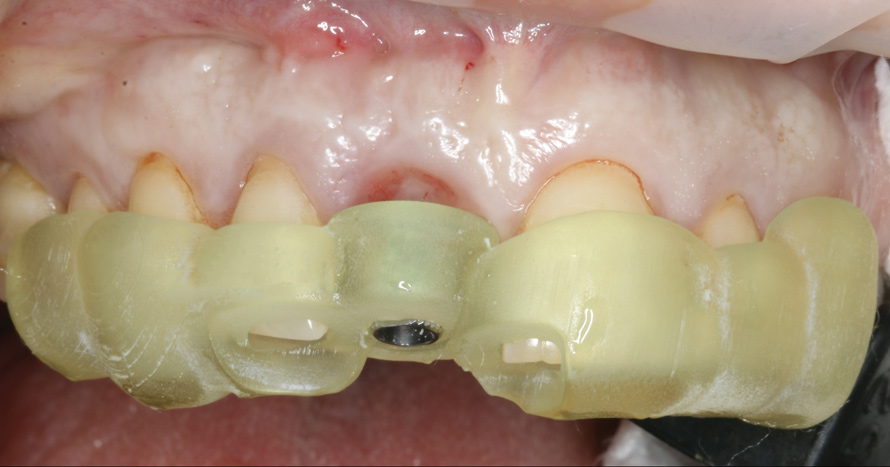

23. Facial view, distal view, and radiograph of the acrylic implant-retained provisional restoration placed at the implant uncovering surgery to contour the soft-tissue profile for final restoration. Critical and subcritical contours follow the anatomic crown profile as seen in both the mesiodistal and buccolingual dimensions.

Figure 23

(24.) Facial view, distal view, and radiograph of the acrylic implant-retained provisional restoration placed at the implant uncovering surgery to contour the soft-tissue profile for final restoration. Critical and subcritical contours follow the anatomic crown profile as seen in both the mesiodistal and buccolingual dimensions.

Figure 24

(25.) Facial view, distal view, and radiograph of the acrylic implant-retained provisional restoration placed at the implant uncovering surgery to contour the soft-tissue profile for final restoration. Critical and subcritical contours follow the anatomic crown profile as seen in both the mesiodistal and buccolingual dimensions.

Figure 25